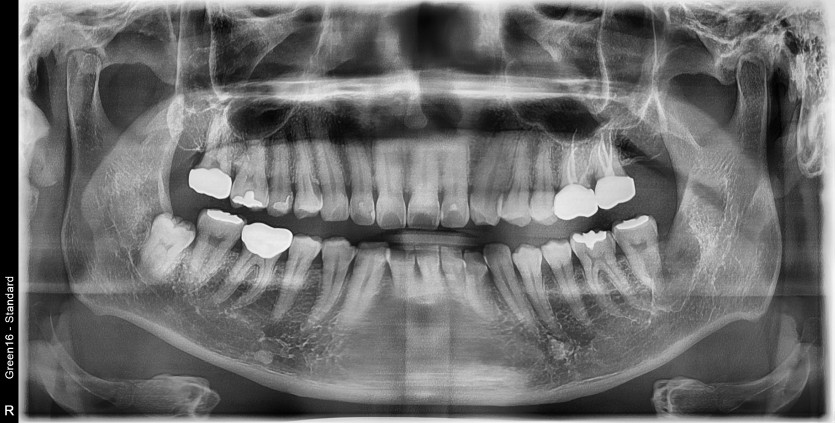

#38 사랑니 발치

구강외과 전문의가 당일발치했습니다.